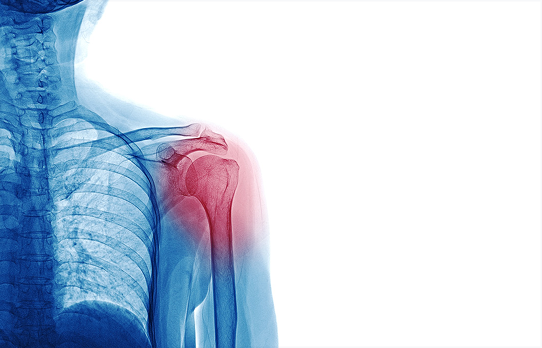

Shoulder Surgery

Orthopedic Specialty Institute specializes in all types of shoulder surgery and repair. Same Day Appointments are now available, please call us today at 954-866-9699 to book a consultation with Dr. Erol Yoldas or Dr. Martin Weaver, or click here to request an appointment online. When considering whether or not shoulder surgery is the correct option for you, it’s important to consult with an expert. Our team offers best-in-class care, as well as innovative, low down time and minimally invasive procedures based on your individual needs. If you are experiencing pain in your shoulders or shoulder, it’s essential to have a professional consult as soon as possible. Shoulder injuries can be severe and time is of the essence in order to treat a serious issue in order to avoid any permanent damage. If you are suffering from shoulder pain, it does not always mean surgery is required. There are numerous pain management options to help you find relief, should your injury be less severe. At OSI, we pride ourselves on taking conservative, effective approaches aimed at restoring the overall quality of life – whether your injury is mild, or extreme. Our combined expertise and individualized care is what sets our team apart, and we encourage you to come in and experience the OSI difference today.